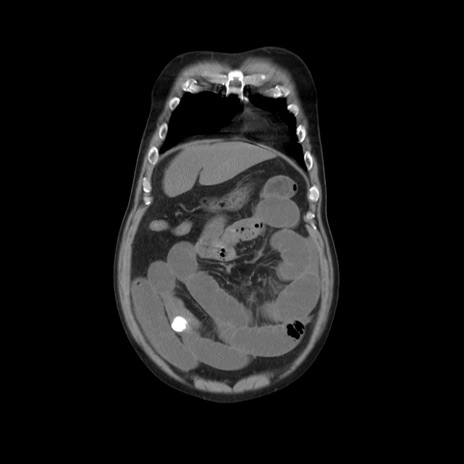

症例20(冠状断像)

横断像